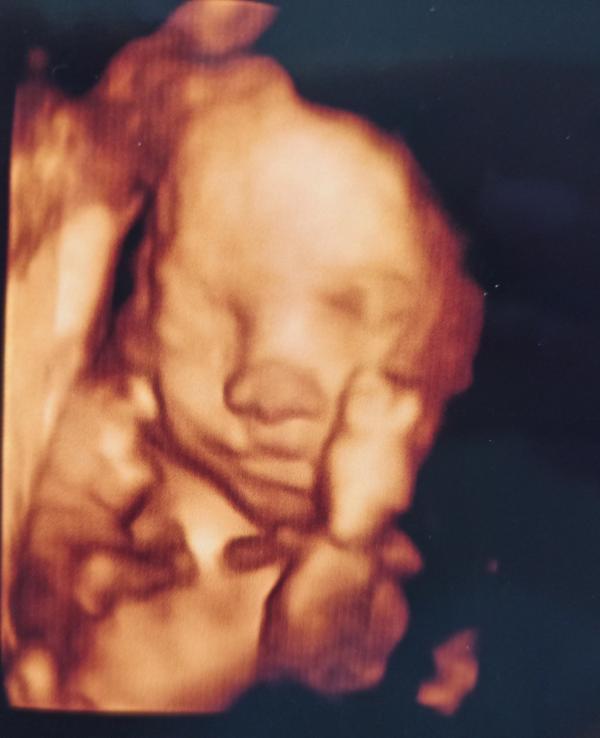

Мой носастенький любимый мальчик 🥰🥰🥰 сделали эхо-сердца, ттт, все отлично😘

Вчера были на эхо сердца, я думала сын вылезет и датчиком настучит узисту😅очень ему все эти узи не нравятся,пинается сильно